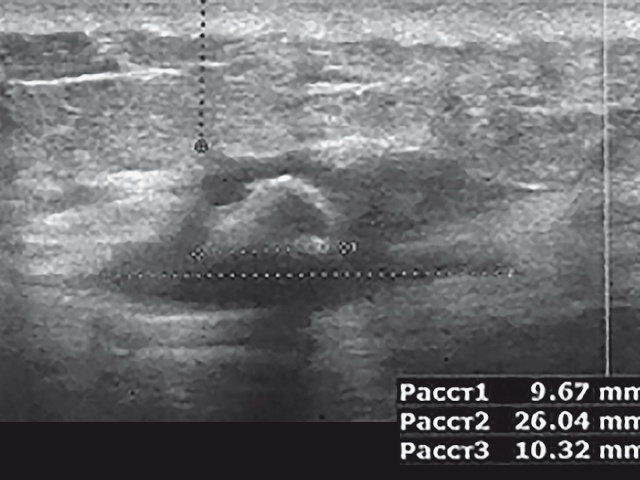

Атерома На Узи Фото